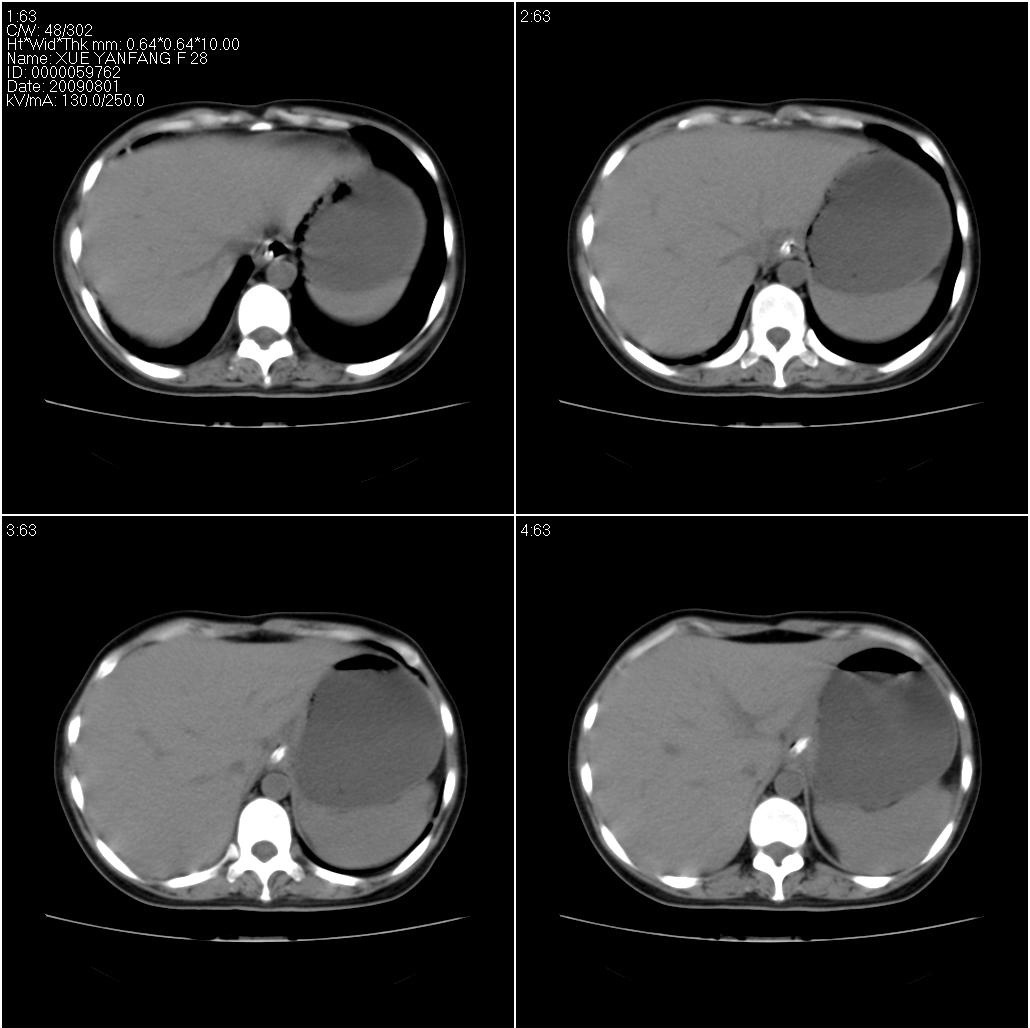

女性,33岁。4个月前因妊娠发现盆腔肿物。ca-125: 1100

胃幽门部癌伴小弯侧和腹腔淋巴结转移,胃内有胃管。

有明显淋巴结吗?我们感觉像是胰腺和胃窦。不过,胰腺尤其是胰头较大,不知道是否正常?

胃窦贲门胃小弯好像都厚啊 ,胃窦处比较明显,而且胃腔扩张明显,考虑胃癌伴梗阻。

未见明显肿大淋巴结,另肝脾大

高密度影是胃肠减压的管子。

支持;胃癌【浸润】幽门梗阻.胰头、胆囊及肝左叶受侵,副脾.